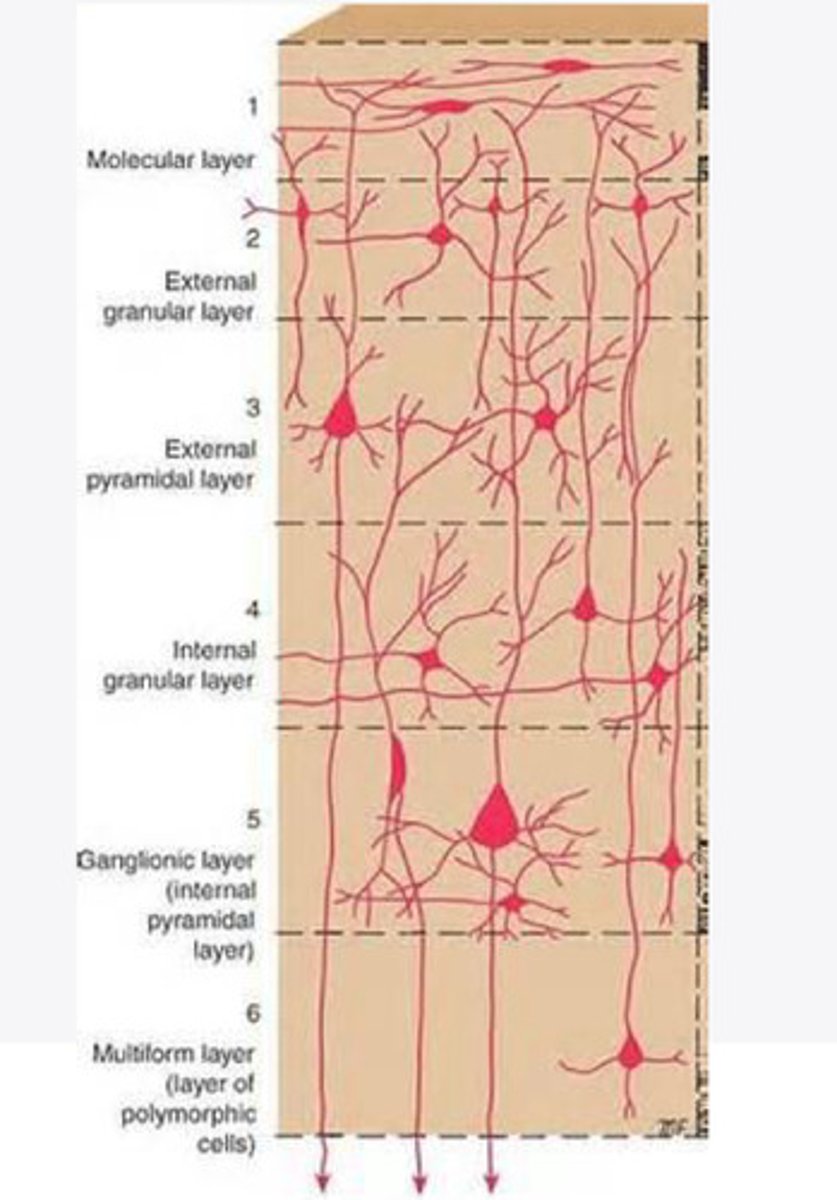

divided into 6 distinct layers, due to varying densities of cell body types within each layer

The cortex of the brain is divided into how many layers? Why is it divided into layers?

Layers of the cortex of the brain pic

2 and 4

What are the layers of the cortex that are associated with input?

3 and 5

What are the layers of the cortex that are associated with output?

molecular layer

What is the name of Layer 1 of the cortex of the brain?

very few cells

Does Layer 1 of the cortex have a lot or few cells?

receives dendrites from internal layers so it may actually function as a coordinating center where layers can communicate action

What does Layer 1 of the cortex do?

1

Every layer sends densities to Layer ____?

1

What layer serves as the "water cooler" of the brain?

external granular layer

What is the name for layer 2 of the cortex of the brain?

receives input from other cortical regions

What is the function of Layer 2 of the Cortex of the brain?

Stellate

What type of cells (stellate/pyramidal) would be most concentrated in Layer 2?

external pyramidal layer

What is the name for layer 3 of the cortex of the brain?

sends output to the other cortical layers

What is the function of Layer 3 of the cortex of the brain?

pyramidal

What type of cells (stellate/pyramidal) would be most concentrated in Layer 3 of the brain?

Layers 2 and 3

What layers are associated with association and commissural fibers?

Layer 3 - axons of cell bodies

Layer 2 - synapse into target areas in Layer 2

What part of the axons is in Layer 2/ in layer 3?

Layer 3 - external pyramidal layer

All axonal cel bodies for association and commissural fibers lie within what layer of the Cortex of the brain?

internal granular

** or called the striate cortex because it is so thick that you can see a line through this layer even in unstrained brain slides

What is the name for the 4th layer of the cortex of the brain?

receives input from the thalamus, geniculocortical layer, and other brainstem areas

What is the function for the 4th layer of the Cortex of the brain?

very thick within the vision, auditory, and somatosensory areas

Is Layer 4 thick or thin within SENSORY areas of the cortex?

Internal pyramidal

What is the name for Layer 5 of the cortex of the brain?

sends axons to the brainstem (corticobulbar) and spinal cord (corticospinal)

What is the function of Layer 5 of the cortex of the brain?

in motor areas of the cortex?

Where is layer 5 very thick in the brain?

the frontal lobe -- very motor heavy

What lobe of the brain will have a thick layer 5 of the cortex of the brain?

the multiform layer

What is the name of layer 6 of the cortex of the brain?

-sends axons back to the thalamus through corticogeniculate fibers

-modulates what information the thalamus sends to the cortex to control the strength of the signal received and modulate what you pay attention to

What is the function of layer 6 of the cortex of the brain?

no

Is layer 6 a motor layer?